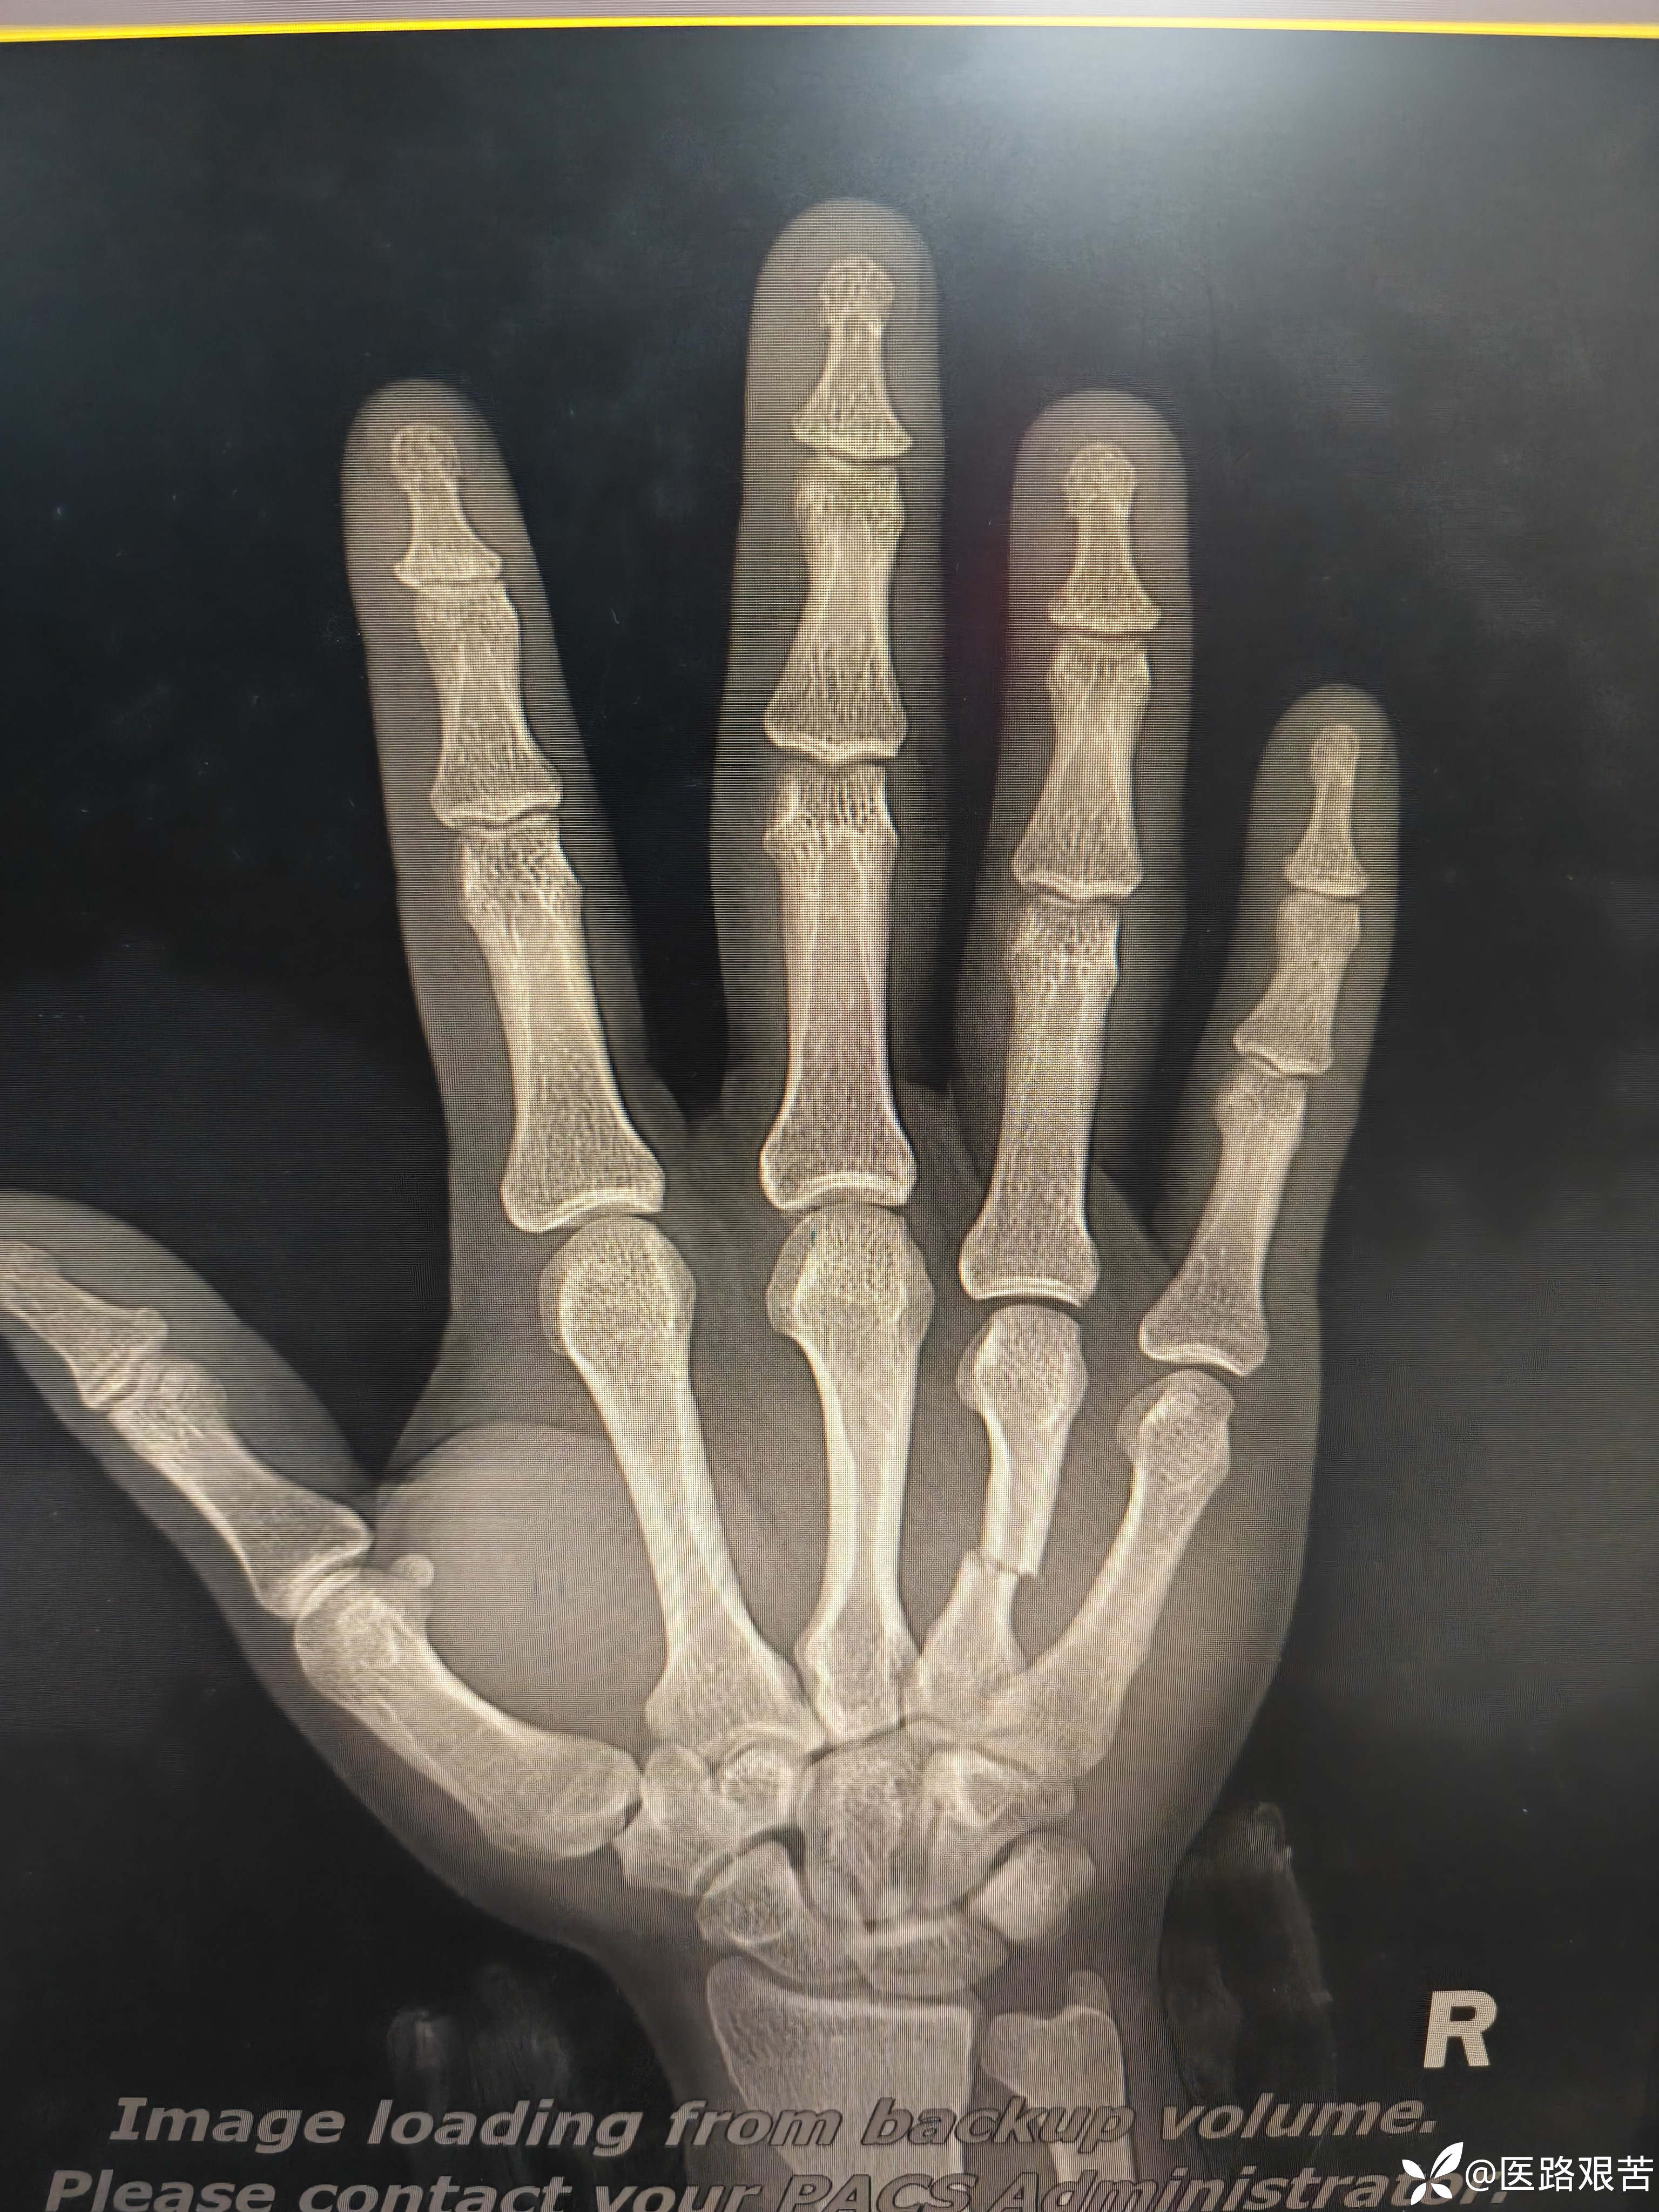

患者,男,32岁,外伤摔倒致右手第四掌骨骨折,伤后1天就医,手法复位石膏固定后,表示骨折立线正,可接受,愈合时间稍长,患者要求解剖复位,并希望早日活动。

术后